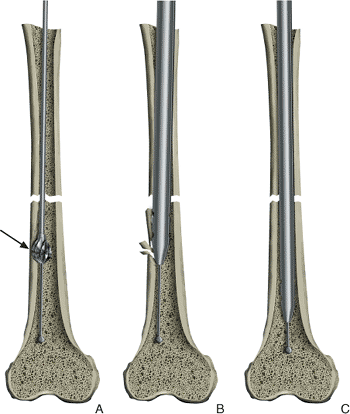

Figures 21.34. A,B.

Ruler measurement. Reestablishing the correct length of the fractured femur and choosing the correct length of the intramedullary nail both require the use of a reference length, which is the distance between the tip of the greater trochanter and the adductor tubercle; this can be measured through use of a radiopaque ruler held lateral to the thigh at the level of the femur. |

Figures 21.35. A,B.

Wire measurement. A second guide wire equal in length to the ball-tip guide wire is inserted into the wound to the level of the entry portal at the top of the femur. A clamp is placed on the guide wire at the point where it overlaps the tip of the ball-tipped guide wire. The distance between the clamp and the free end of the second guide wire is measured and used as an estimate of the distance from the tip of the greater trochanter to the adductor tubercle. This distance is compared with the reference measurement made preoperatively on the contralateral intact femur. Adjustments must be made with traction to correct any discrepancy with this distance. |